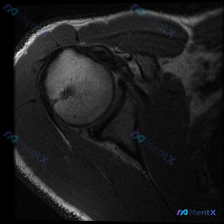

看到一份髋关节MRI T1序列冠状位的病例材料,用户预设想了解盂唇病变的可能性。 先看基础影像分析: - 扫描范围:单侧髋关节区域,包括股骨头、股骨颈、大转子、髋臼及其关节间隙 - T1序列特征:正常骨髓高信号,皮质骨低信号,肌肉中等信号,关节软骨及韧带清晰 - 股骨头/股骨颈:轮廓光滑,未见水肿、...

看到一个髋关节MRI病例,先给大家分享一下核心发现: 影像类型:髋关节MRI冠状位T1加权成像 主要表现:股骨头及股骨颈近端骨髓呈弥漫性T1低信号,与正常脂肪骨髓的高信号形成鲜明对比;髋臼顶轮廓清晰,关节间隙无明显狭窄,盂唇在T1序列上未见明确撕裂征象。 患者主诉提到了“盂唇病变”,但影像核心是骨髓...

整理到一个髋关节MRI分析的内容,仅提供了单张T1序列冠状位图像,临床关注点是盂唇病变。先看一下这张图像的客观描述: 骨骼结构:股骨头圆形,轮廓光整,骨皮质连续,骨髓信号均匀;髋臼形态连续,骨皮质清晰;大转子区域骨皮质完整。 关节间隙:宽度基本对称,无明显狭窄,无异常信号填充。 软骨与盂唇:股骨头表...

整理到一张髋关节T1加权冠状位MRI的病例资料,初始有人提问「能否观察到盂唇病变」。先放这张图的核心影像描述:图像聚焦一侧髋关节,股骨头形态基本呈圆形,股骨头前上方负重区皮质下可见清晰带状低信号影,其余股骨头、颈骨髓信号为正常脂肪高信号,关节囊无明显增厚或积液。 想问问大家:仅看这张图的描述,您第一...